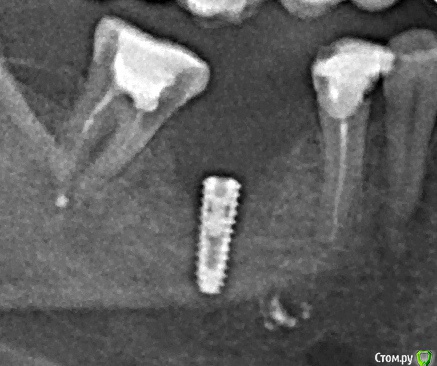

Наталия1966 Опубликовано 17 сентября, 2019 Поделиться Опубликовано 17 сентября, 2019 (изменено) на нижнюю челюсть в место 40 лет отсутствующей шестерки. С расщеплением гребня. Когда боль прошла отек спал и рана затянулась, то над имплантом образовался гнойник. Врач его выдавил, он совершенно безболезненный, ничего не болит, не кровит, кроме этого гнойничка над десной. На снимке мне показался скол кости слева, сильное понижение контура кости. Стоит ли волноваться или имплант все же приживется? Назначен визит через неделю для установки формирователя. Прошло три с половиной месяца Изменено 17 сентября, 2019 пользователем Наталия1966 Ссылка на комментарий

Наталия1966 Опубликовано 17 сентября, 2019 Автор Поделиться Опубликовано 17 сентября, 2019 (изменено) Хорошо бы срезы томограммы. Но , судя по предоставленной информации проблема имеется. И есть тенденции к её развитию.Это пока мой единственный снимок, который я взяла с общего панорамного снимка. Еще делали сразу после установки, но его не распечатывали и что там, честно говоря, я не помню, каков контур кости вокруг импланта. Два месяца вылезали осколки, потом вроде все успокоилось, кроме вот гнойника, на который я не обращала вниманья сначала, но потом он так упорно держится и мешает жевать. В воскресенье я была у доктора, он выдавил гной с гнойника, сказал похоже на гранулему, ничего не болело, даже при выдавливании. Потом дома он надулся здорово и побаливало чуть чуть вокруг, к утру значительно опало. Я обрадовалась, решила, что помогло. Скажите, есть шанс, что имплант приживется или это только вопрос времени его аннуляция. Изменено 17 сентября, 2019 пользователем Наталия1966 Ссылка на комментарий

krokomot Опубликовано 17 сентября, 2019 Поделиться Опубликовано 17 сентября, 2019 нужен прицельный снимок, на томограмме невозможно оценить состояние кости вокруг металлического объекта. Гнойник, возможно заглушечный свищь. установится формирователь станет яснее. 2 Ссылка на комментарий